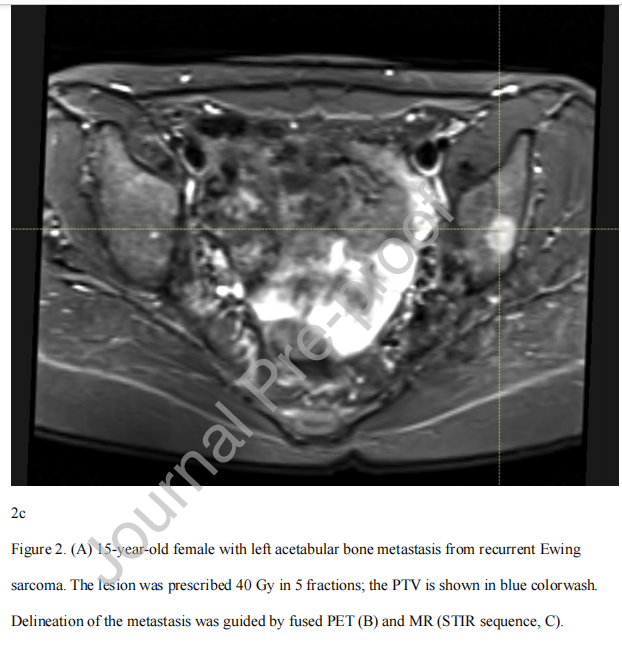

对于SBRT靶体积,没有标准的轮廓方法。具体来说,考虑到靶点解剖位置的异质性和肿瘤类型的放射敏感性,关于是否需要临床靶体积(CTV)扩大没有明确的指南。对于化疗后的骨靶区,可考虑采用COG入路,其总靶体积等于化疗后体积加上化疗前骨异常,CTV为解剖受限的1 cm体积外扩(NCT02306161)。对于完整的骨转移,可以考虑国际共识性的成人非脊柱骨转移CTV指南,对于完整的脊柱转移,也可以考虑国际脊柱放射外科靶体积勾画指南。然而,年轻患者的靶体积可能很复杂,并且某些特征如硬膜外疾病、脊柱旁疾病、靶体积大和软组织疾病可能会使患者面临较高的失败风险,因为靶区勾画存在挑战。在可行的情况下,建议使用多种成像方式,如CT、代谢成像(PET)和MRI;图2提供了一个示例。如果可能的话,放射肿瘤学家应该注意避免在骨骼不成熟的儿童中使用骨骺生长板,尽管应该避免损害肿瘤的覆盖范围。

图2。 (A)复发性尤文氏肉瘤左侧髋臼骨转移的15岁女性。病灶分5次给予40 Gy;PTV显示为蓝色。通过融合PET (B)和MR (STIR序列,C)定位转移灶。